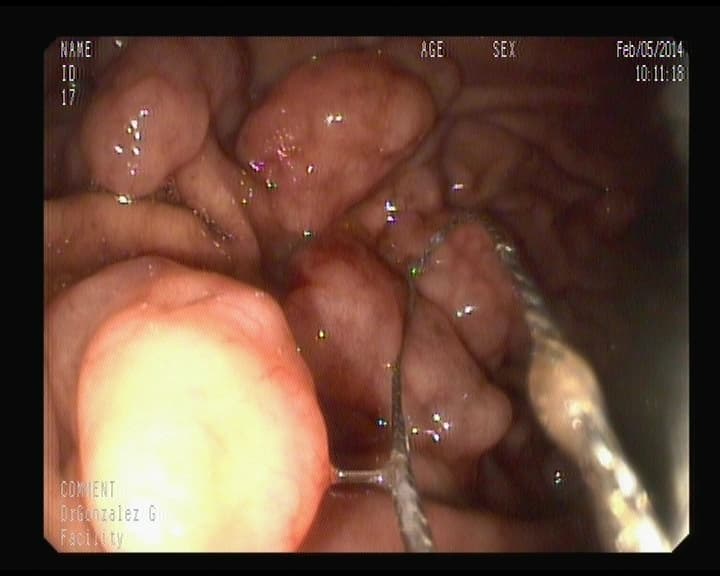

Punto sangrante anterior foto, ya solucionado.

Resultado del punto sangrante en duodeno ya tratado.